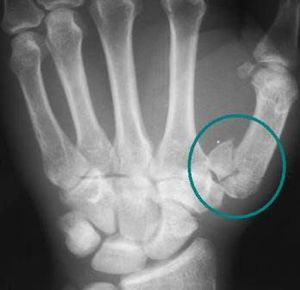

Name the fracture

😊😊Rolando Fracture